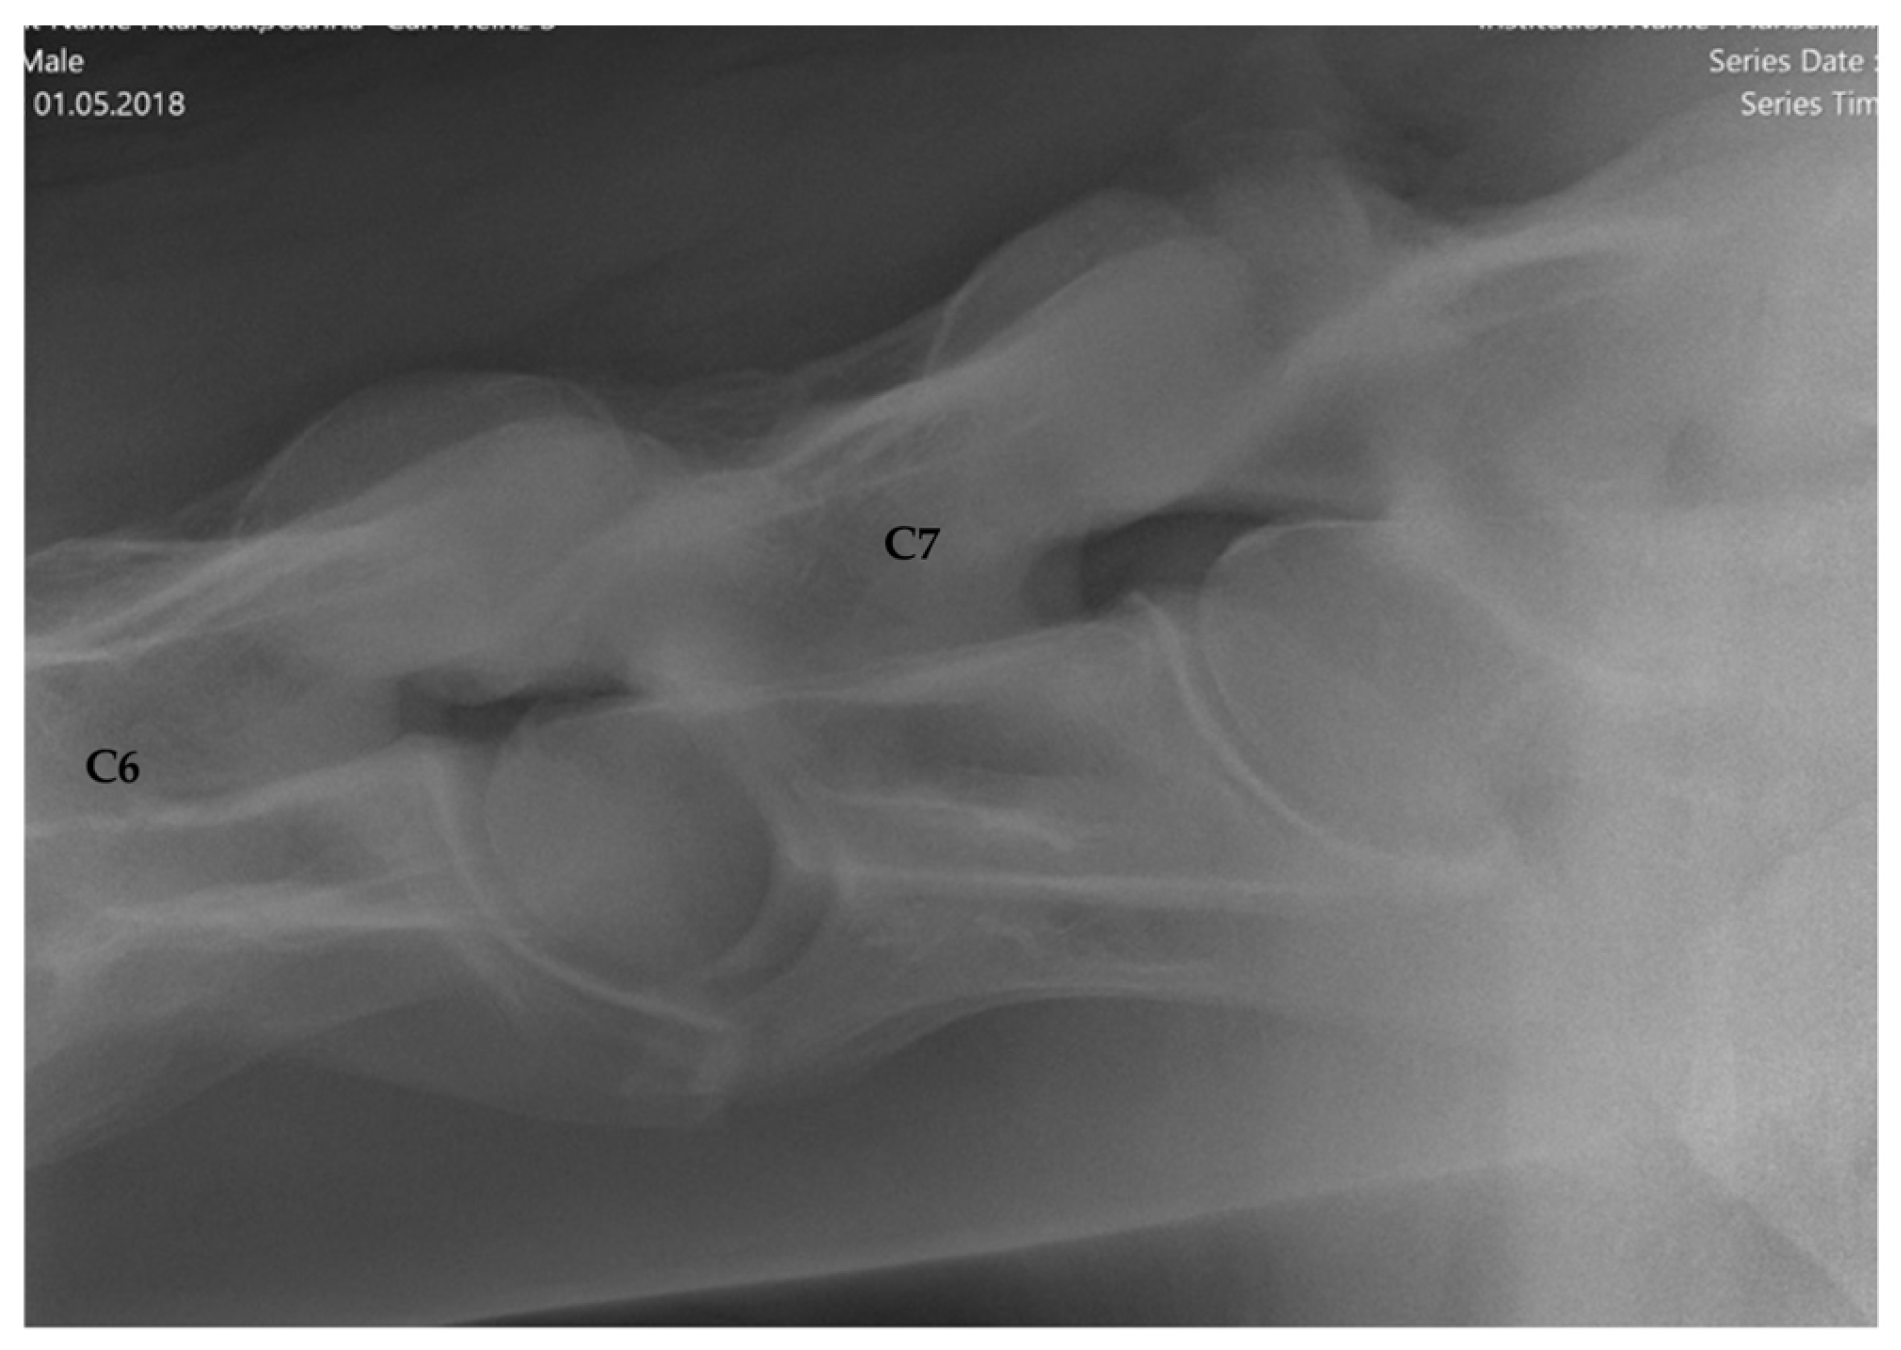

2.1.2. Radiographic Assessment

- Group 1 = normal: no periarticular new bone formation at ventral margins of APJ, intervertebral foramina clearly visible.

- Group 2 = mild APM: minimal/equivocal enlargement and sclerosis of APJ with mild osteophytosis ventrally, intervertebral foramina open/slightly obscured by new bone formation.

- Group 3 = moderate/severe APM: clear enlargement and sclerosis of APJ with moderate osteophytosis ventrally, significant reduction/loss of intervertebral foramina.